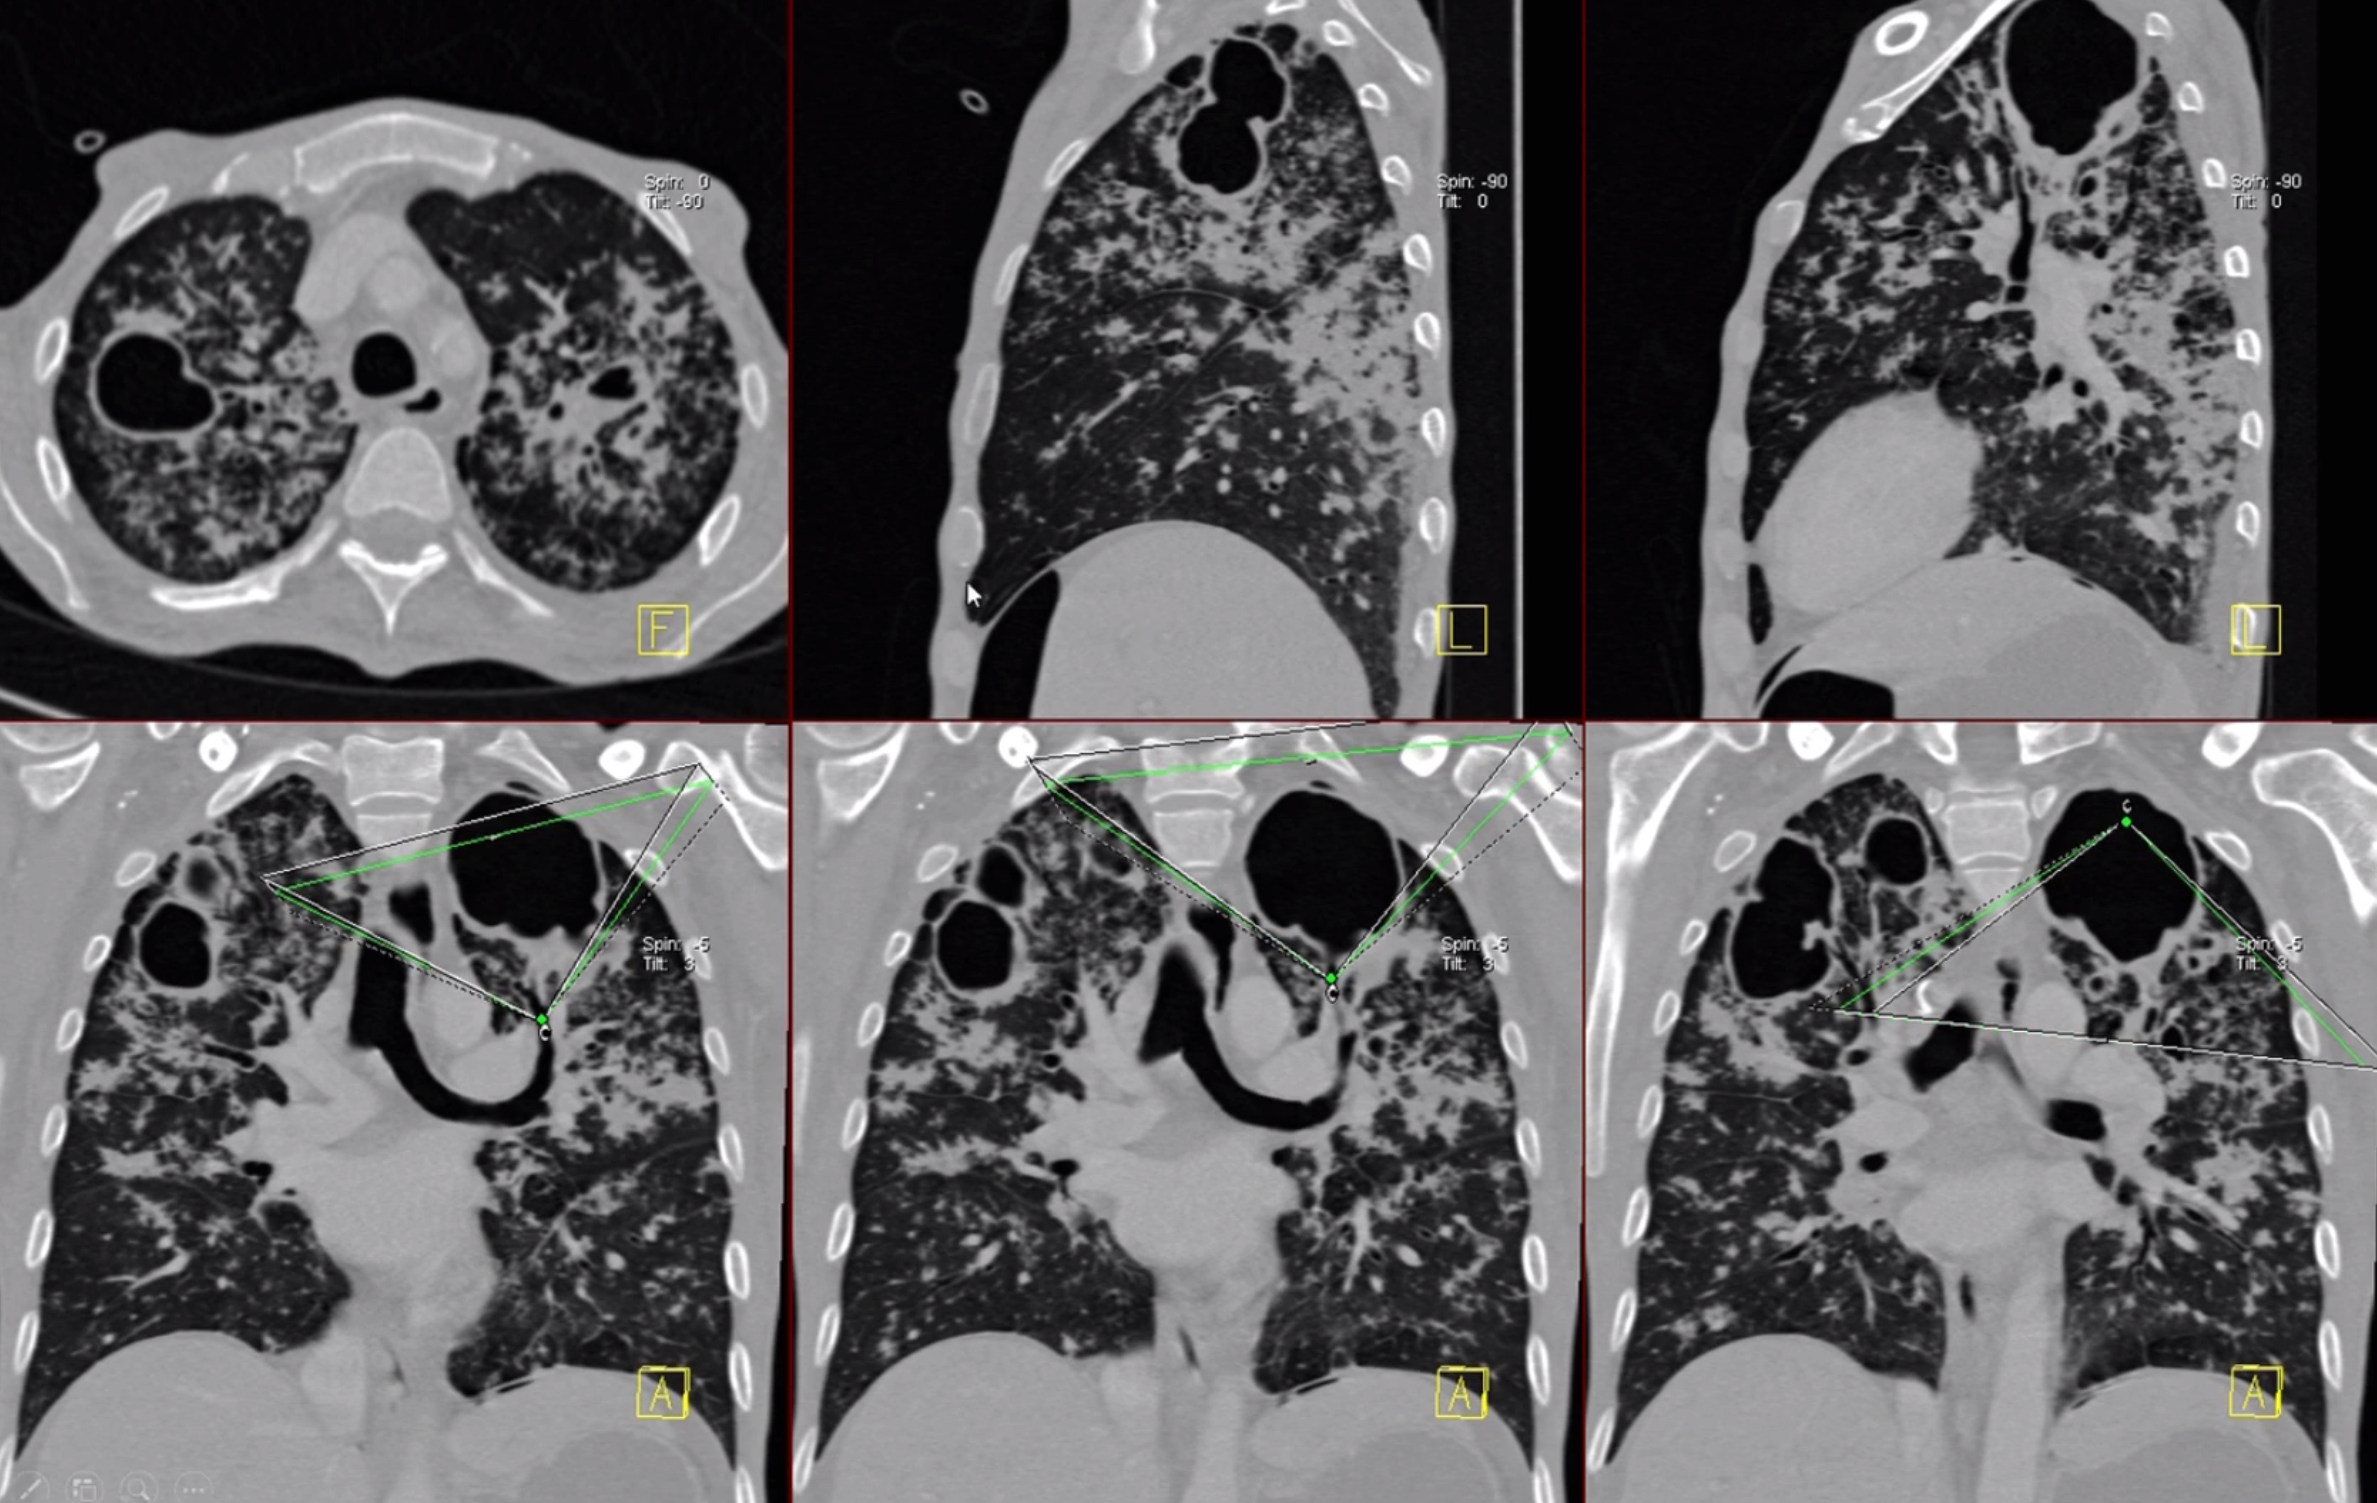

Možnosti rtg diagnostiky

image